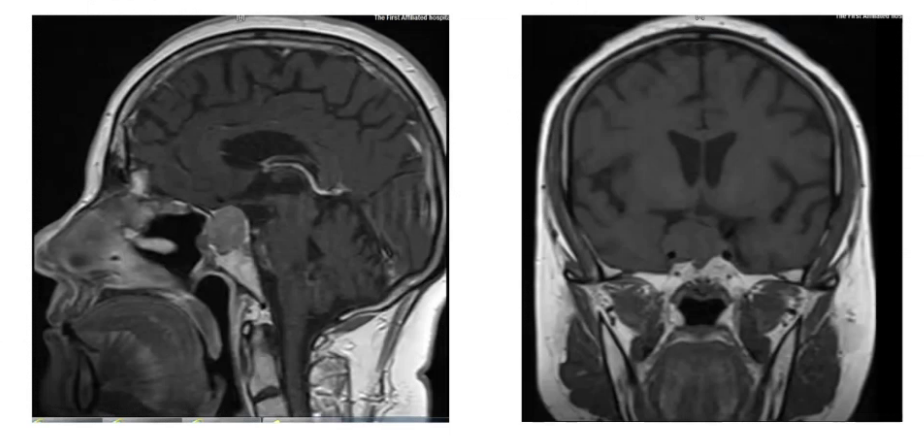

2022年5月垂体核磁平扫及增强:结合病史垂体瘤术后改变,现垂体右缘异常强化灶,与2019.4.15前片相比病变体积较前增大,请结合临床随诊。(增强扫描鞍区右缘可见稍低强化结节,矢状位测其范围约2.22cm×2.17cm, 右侧颈内动脉海绵窦段被包绕,垂体柄向左侧偏移,视交叉位置正常;左侧颈内动脉海绵窦段未见明显异常)。

2023年3月垂体核磁平扫及增强:1.结合病史垂体瘤术后改变,现垂体右缘异常强化灶,与2022.5.26前片相比病变体积较前增大。管状位测其大小约2.55cm×2.12cm,右侧颈内动脉海绵窦段被包绕。

2024年10月垂体核磁平扫及增强:鼻窦及鞍底骨质信号不连续,术区结构紊乱,呈术后改变,正常垂体形态消失,垂体右缘可见片状稍长T1混杂长T2信号,垂体柄向左侧偏移,增强扫描垂体右缘可见片状未强化区,冠状位较大层面测其大小约为0.81cm×0.67cm。